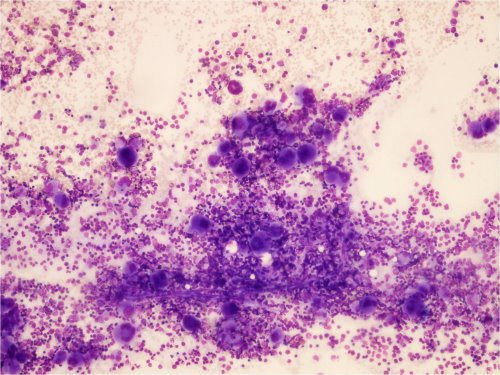

Aplastinen anemia

• Kohtalaisen harvinainen lapsilla

• Luuytimen kaikki linjat (erytropoieesi, myelopoieesi, trombopoieesi) ovat hypoplastisia tai aplastisia.

• Perifeerisessä veressä normosytäärinen anemia, leukopenia ja trombopenia

Kuva 1. Vaikea aplastinen anemia, yleiskuva. Näkyy rasvaa ja stroomaa, mutta ei juurikaan hematopoieesia.